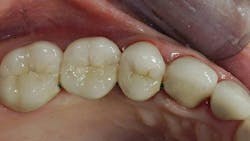

My suggestions are based on the dental literature and my many years of practice experience. Consider the factors below to help you decide whether pins or posts are needed. Figures 1–3 show the need for the restorative buildup procedures.

A general rule to determine if a tooth needs a buildup is related to how much coronal tooth structure is not present. If one-half or more of the coronal tooth structure is missing and most of the remaining tooth is dentin only, placing a buildup is advised. If a buildup is needed, frequently pins should be placed to provide long-term retention of the material to the dentin. Additionally, most agree that about 2 mm of near-parallel tooth structure should be remaining circumferentially coronal to the prep margin to provide a ferrule effect for retention.